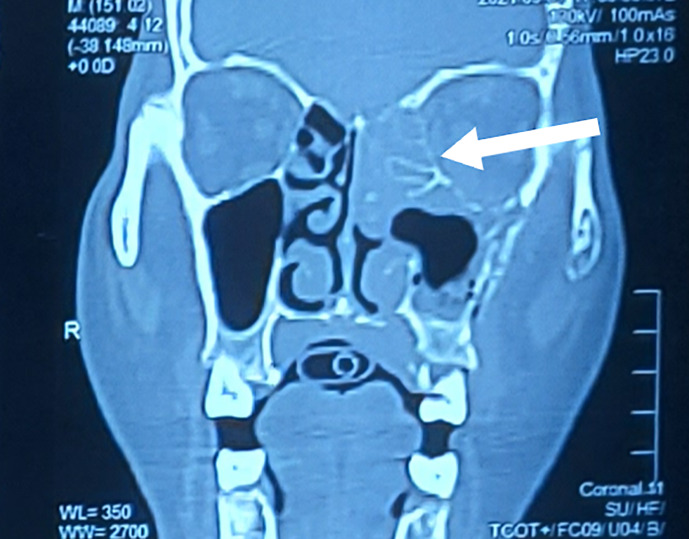

Case presentation: We hereby present the case of a 55-year-old man with a history of diabetes mellitus (potential impact on COVID-19 severity discussed in the supplementary material) presenting with altered sensorium, swelling in the left eye, and involuntary jerky limb movements. Neurological examination revealed neck rigidity, myoclonic jerks, and an extensor plantar response. Brain magnetic resonance imaging (MRI) was performed, which revealed cortical enhancement in the bifrontal, temporal, and occipital lobes. Rapid progression of myoclonus, altered sensorium, and cortical enhancement on MRI suggested Creutzfeldt-Jacob disease. After a thorough workup, the diagnosis was COVID-19 encephalitis with rhino-orbital mucormycosis. The treatment regimen consisted of adequate glycemic control, remdesivir injection, intravenous and retroorbital liposomal amphotericin, and levetiracetam. The patient's condition improved, and he was eventually discharged.